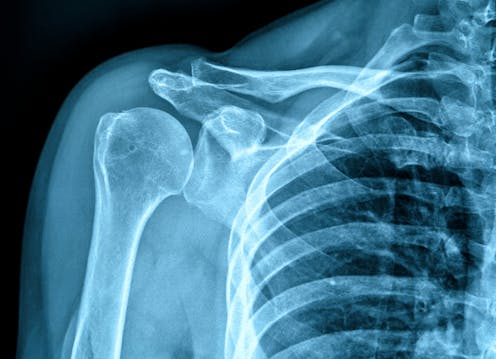

Dental development is done by using a dental x-ray of the person and then comparing the development of the teeth to images of dental development from children of similar age and same sex. This can then provide what is called a “dental age”. Skeletal maturity is assessed using imaging techniques such as x-rays or computer tomography, a combination of several x-ray images of the body part.

Commonly used is a hand and wrist x-ray, which is compared to a series of developmental charts, again from children of known ages and same sex. This method is already used in the UK for clinical purposes as a reliable method for assessing issues such as growth hormone deficiency, or early or delayed puberty.

Some have criticised these methods for exposing children to unnecessary radiation that does not have a medical therapeutic purpose, although MRI imaging can be used instead of methods involving radiation. However, the radiation dose from a dental x-ray or a hand and wrist x-ray is very small. A small dental x-ray will yield the same radiation as we get in a day from our environment.